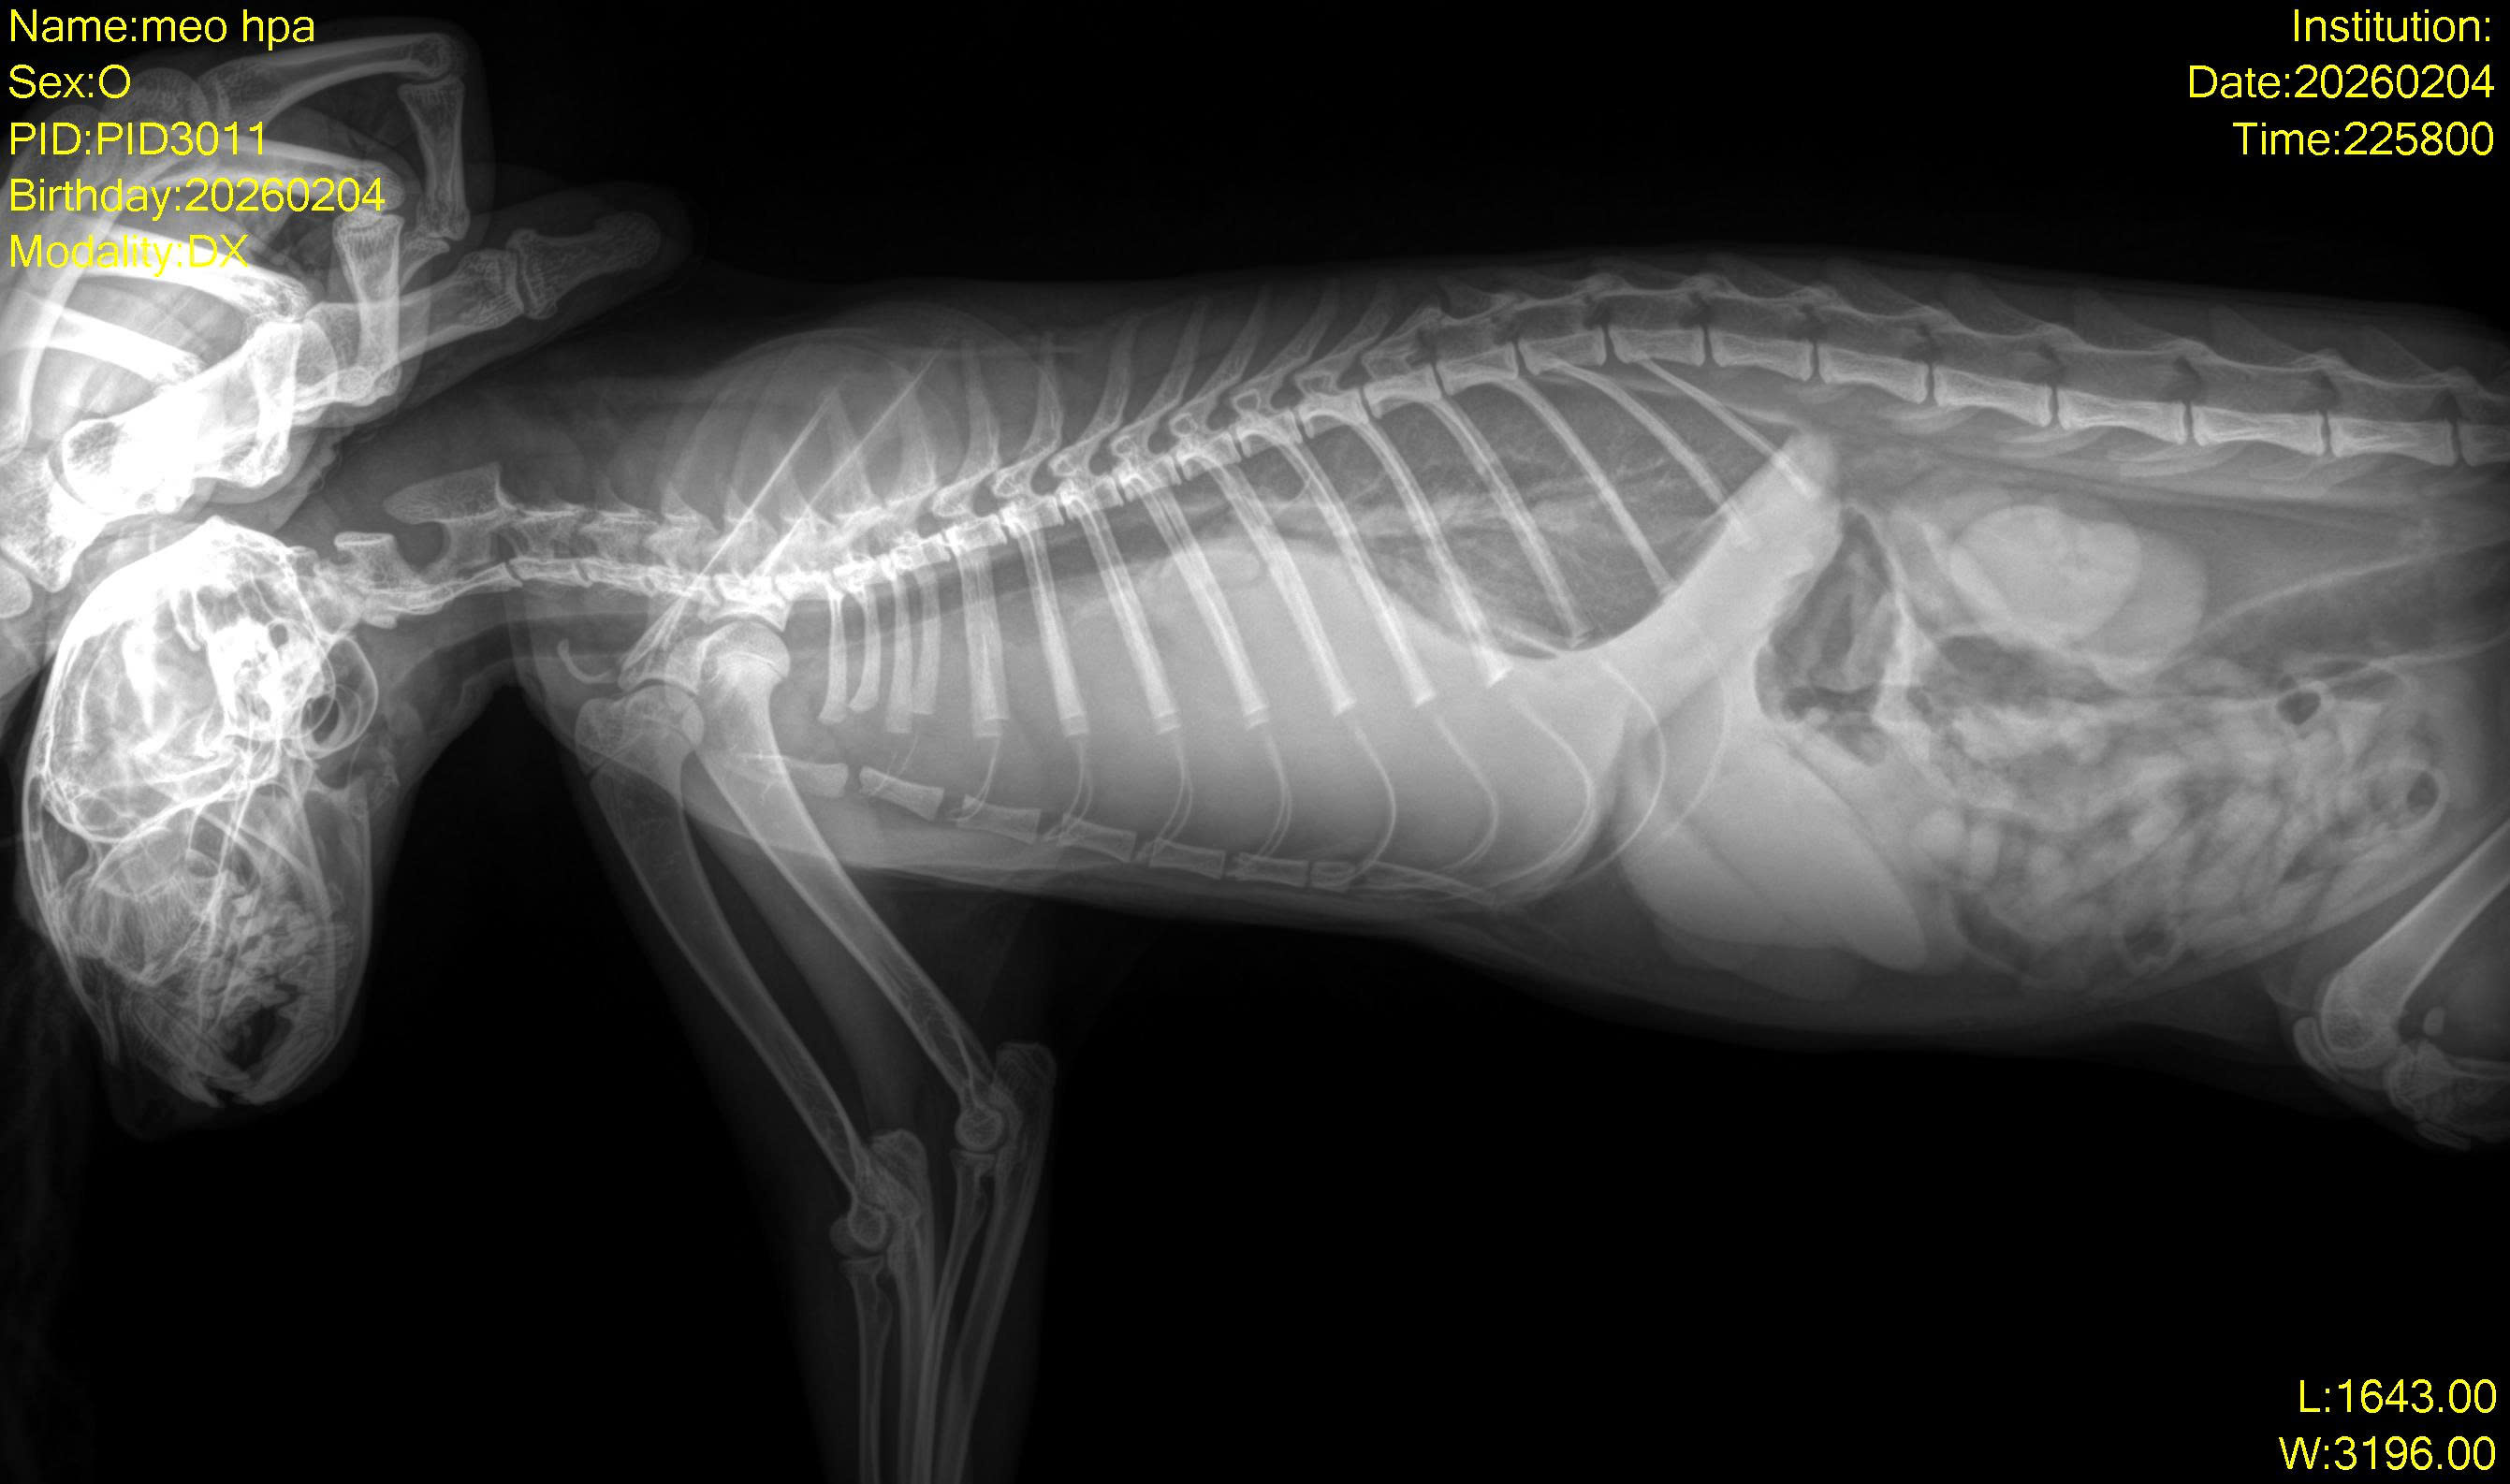

Bé được 1 bạn nhặt được ngoài đường. Bị khó thở, yếu. Đưa đến Solpet, chụp x-quang thấy tràn dịch màng phổi.